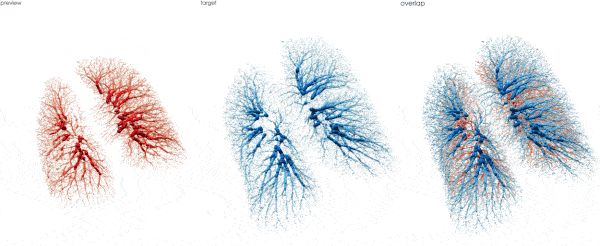

肺部血管树点云匹配(呼气-> 吸气)

这里我们分别用 Nearest Neighbor 和 OT 来匹配一对树状结构

(严谨的来说这里我加了后期的smooth 来regularize transformation, 但在这里不是重点)

Fig 2.1. NN tree registration.

Fig 2.2. OT tree registration.

上面是 NN 的结果, 不出意料被 local trap 了,因为它是对每个source point 匹配target中的最近点, 下面是OT的结果,它用到了全局信息所以匹配的很好。